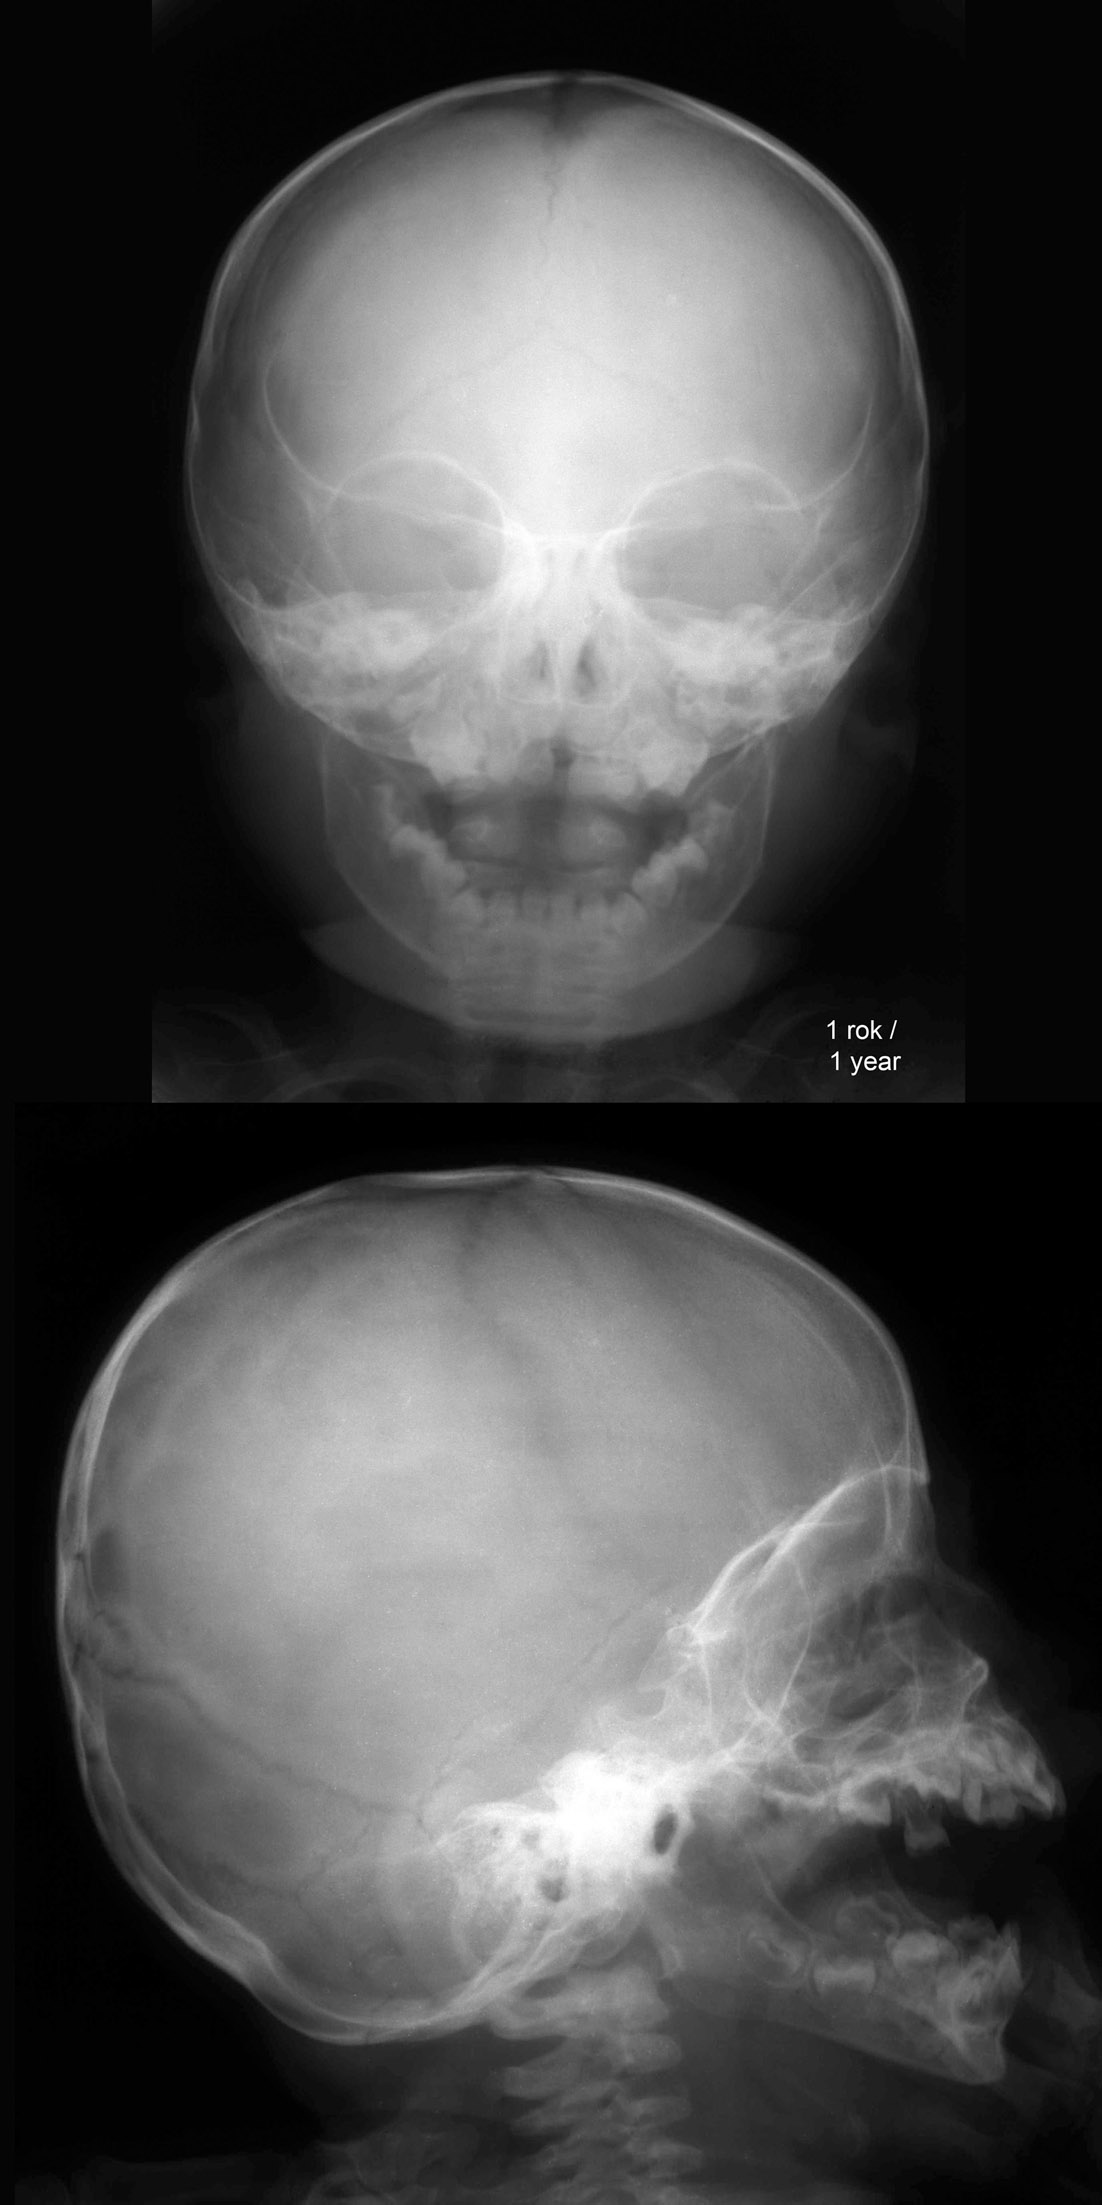

RTG głowy rocznego dziecka.

RTG głowy dziecka w okresie

od 8 mies. ciąży do 1 roku.